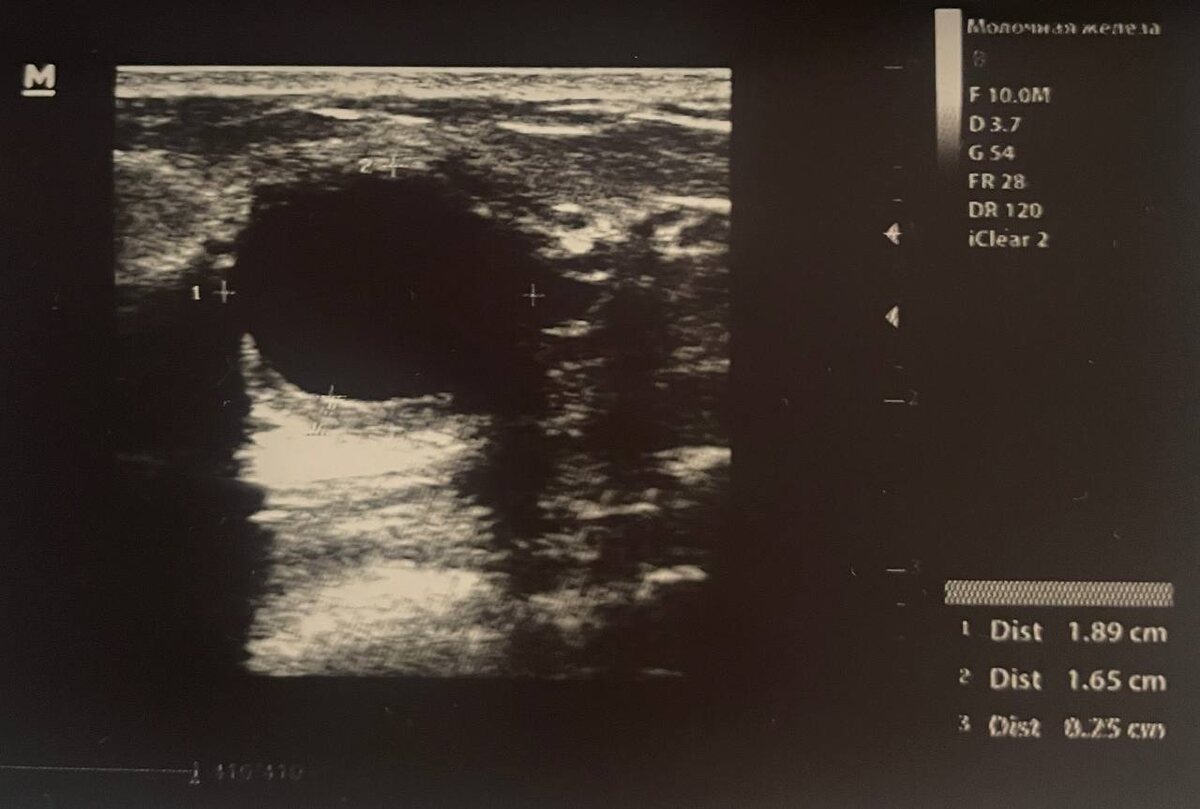

При воспалении кисты молочной железы в ней не обязательно будет определяться эхогенная взвесь. В данном случае визуализируется воспалительная инфильтрация стенки кисты при вполне однородном анэхогенном содержимом. У пациентки множественные кисты молочных желёз, некоторые из которых периодически воспаляются. Кисты могут нагнаиваться из - за гормональных нарушений, заболеваний, вызывающих снижение иммунитета, травм или даже стресса - который может вызвать дисбаланс гормонов, в том числе половых. #кистамжузи

При воспалении кисты молочной железы в ней не обязательно будет определяться эхогенная взвесь. В данном случае визуализируется воспалительная инфильтрация стенки кисты при вполне однородном анэхогенном содержимом.

У пациентки множественные кисты молочных желёз, некоторые из которых периодически воспаляются.

Кисты могут нагнаиваться из - за гормональных нарушений, заболеваний, вызывающих снижение иммунитета, травм или даже стресса - который может вызвать дисбаланс гормонов, в том числе половых.